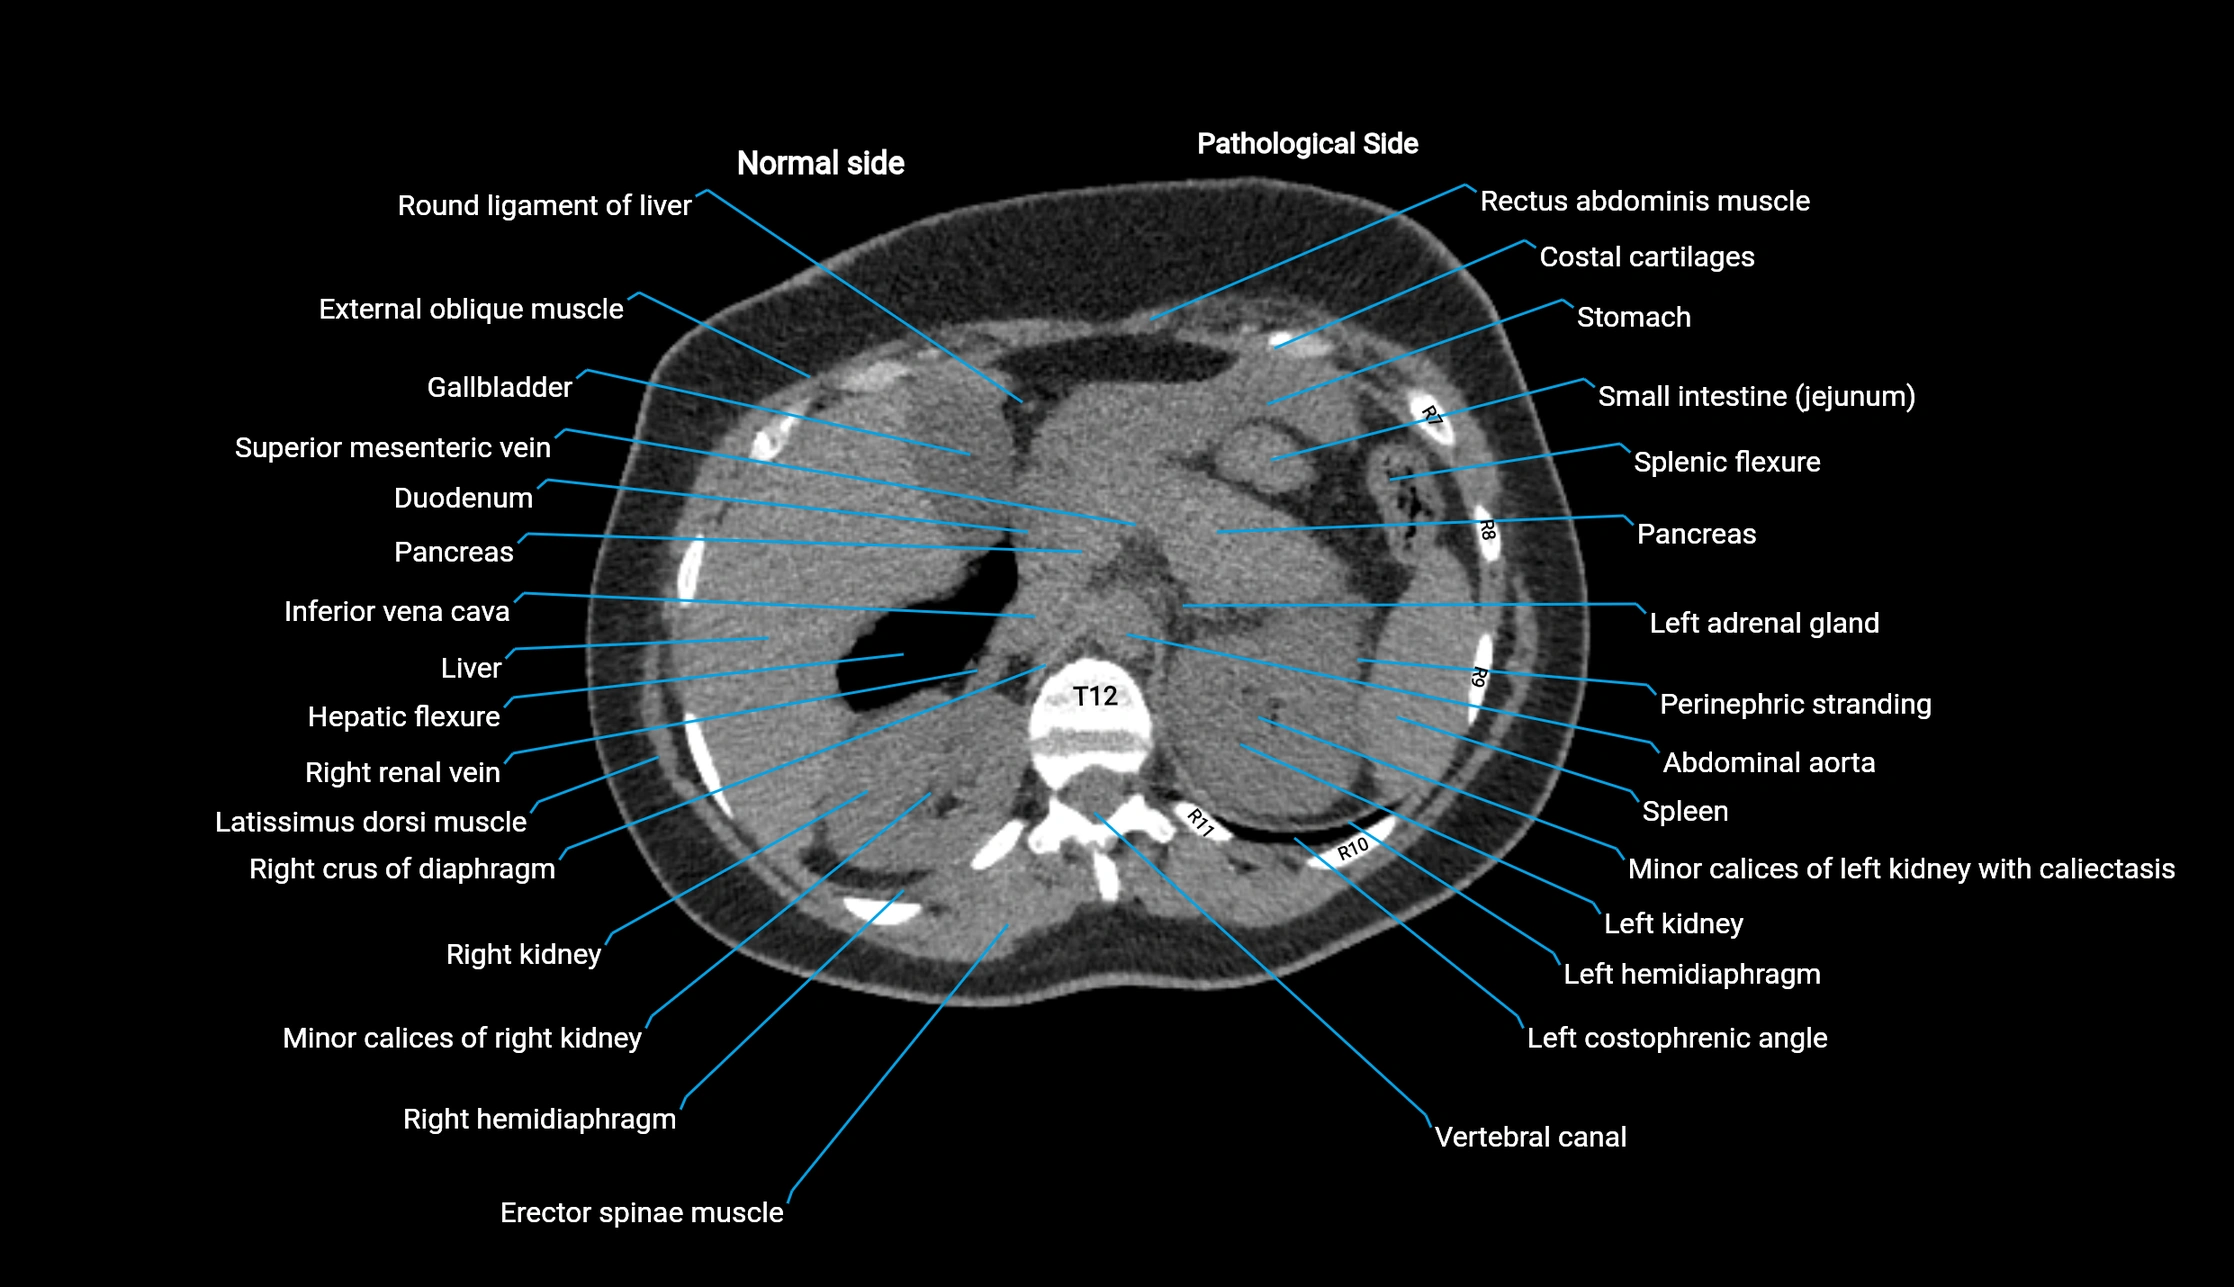

CT image

image